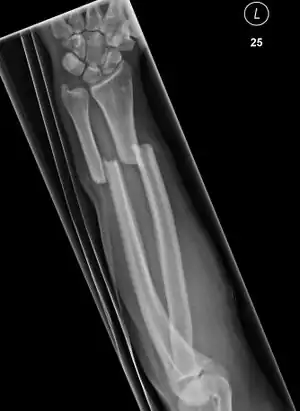

Updisplaced isolated ulna fracture

Front view of bowing fractured radius and ulna

Side view of bowing fractured radius and ulna